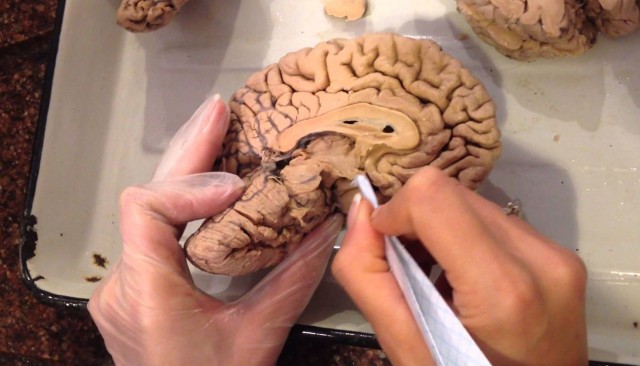

В человеческом мозге обнаружена неизвестная прежде структура, названная учеными научно-исследовательского института неврологии Австралии (Neuroscience Research Australia) ядром веревчатого тела (endorestiform nucleus). Пока никто не знает функций этого образования. Об этом сообщает издание Science Alert.

Известно, что ядро расположено в нижней ножке мозга (веревчатого тела), это сгусток нервных волокон. По нему от спинного мозга в мозжечок идут импульсы. Тело при этом регулирует осанку, равновесие и движение тела.